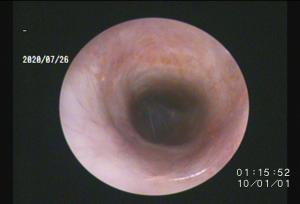

正常な耳内はこのように綺麗です

上記の写真は正常な耳道の写真です↑